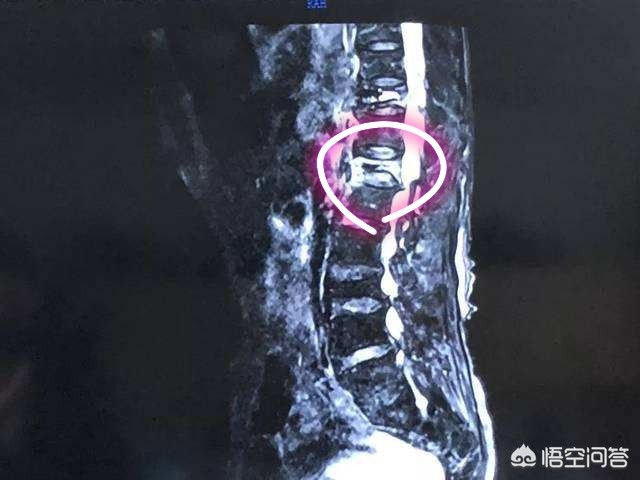

第五,骨盆前倾的患者不建议做燕飞。大家看到下图就会理解骨盆前倾是一个什么样的状态。

拥有这样身材的女性朋友都会有一个共同的特点,那就是拥有一个漂亮的翘臀。但是骨盆前倾相当于是我们脊柱的曲度明显的变大。

如果骨盆前倾的患者产生了腰痛,做燕飞康复的话,整个椎体是像背侧伸展,那么这种动作会加大骨盆前倾,对患者不利。